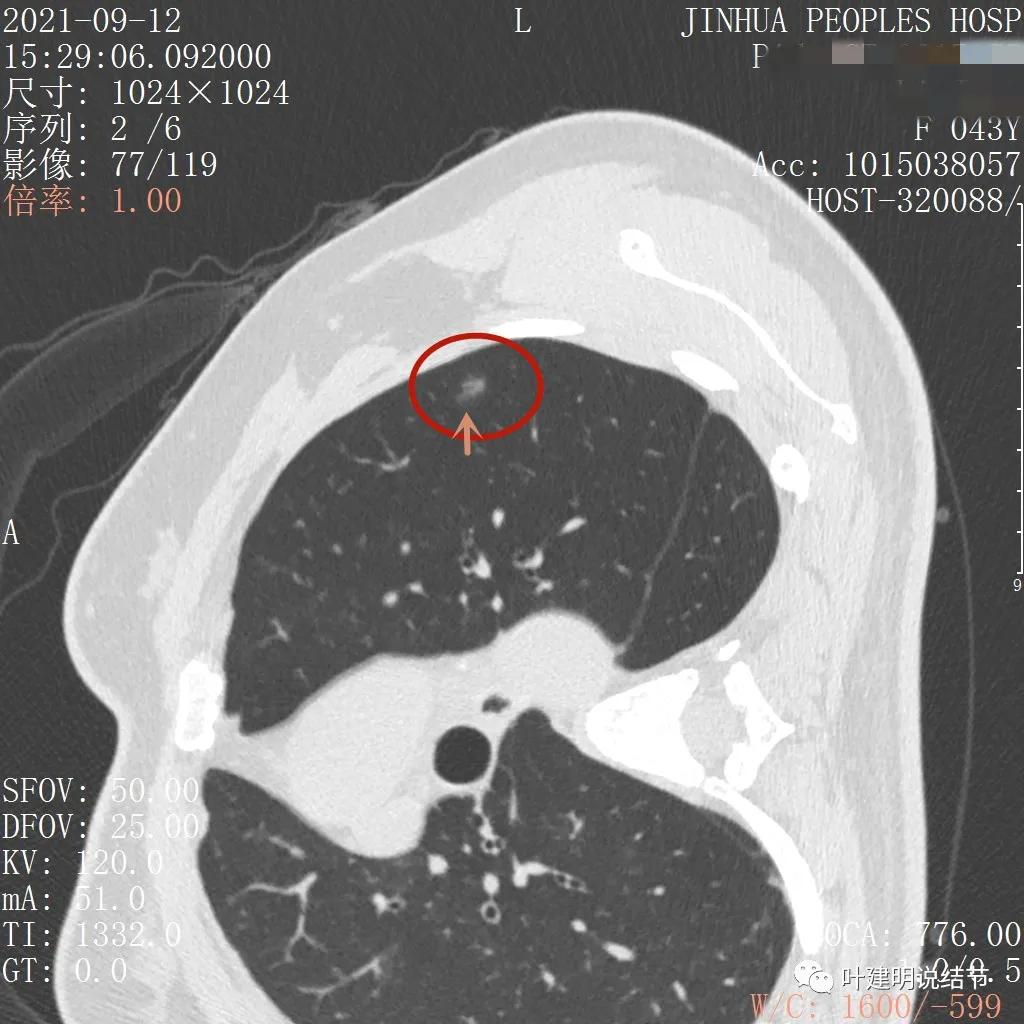

上图非常不舒服,病灶边缘有毛刺(蓝色箭头),中间有偏实性成分(粉色箭头所指),整体看密度不均杂乱

上图示明显的血管进入(桔色箭头),而且进入病灶后散大模糊,不是穿行;病灶内有高密度区域(粉色箭头)。但事后分析,绿色箭头所指的磨玻璃部分密度仍是过低,且边缘显模糊,与浸润性腺癌可能不是太符合。

以上三图均示典型的混合磨玻璃,实性成分杂乱,整体密度杂乱,并有血管征,是较为典型的浸润性腺癌影像表现。

看了后处理重建的图像,我们认为基本上应该就是浸润性腺癌了,从平扫到靶扫到靶扫描后处理,一步一步往更恶性的角度考虑。某A按我们的建议进行了单孔胸腔镜下手术,结果术中快速病理切片示:原位腺癌。我还觉得术后病理会不会升级,所以还在等石蜡切片,因为影像上,特别是后处理重建的图像太像浸润性腺癌了,结果仍是原位腺癌: